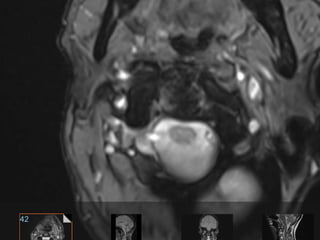

55 year old woman with central axial neck pain with

no radiculopathy; no signs or symptoms of myelopathy.

No history of trauma PMH: hypothyroidism in general

healthy

55 year oldwoman with central axial neck pain with no radiculopathy; no signs or symptoms of myelopathy. No history of trauma PMH: hypothyroidism in general healthy